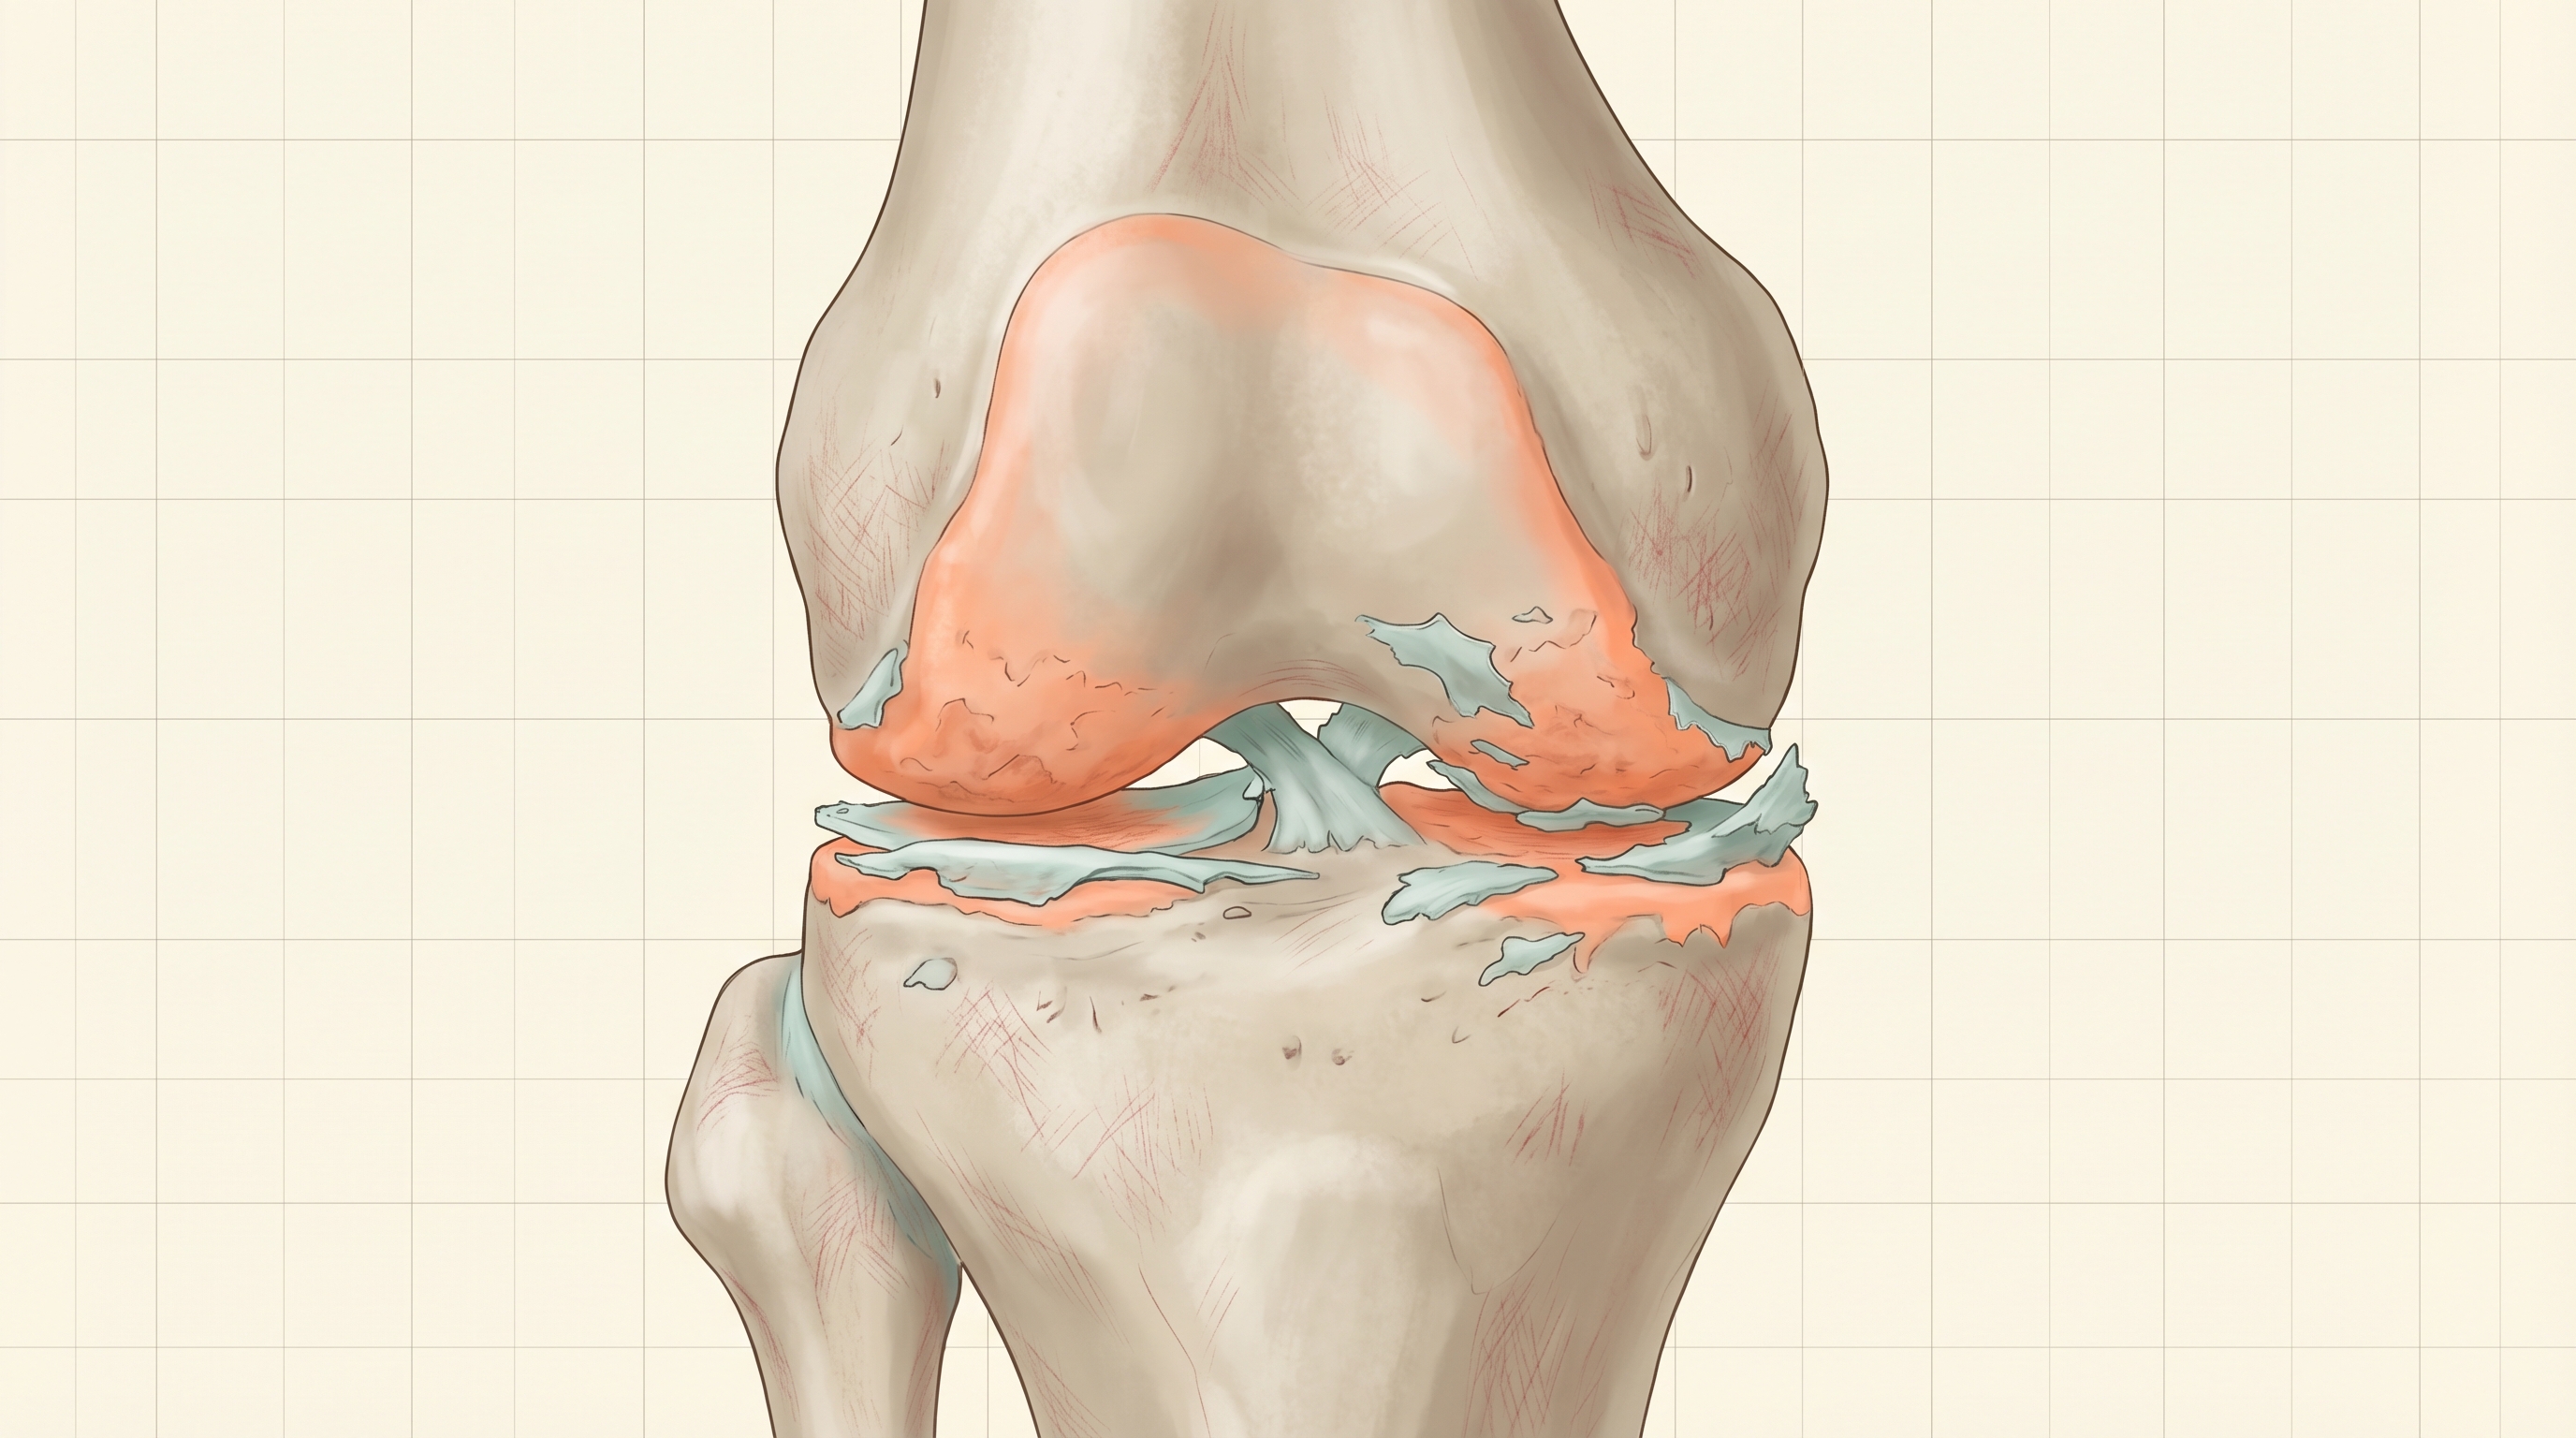

Comprehensive guide to 10 evidence-based alternatives to knee replacement surgery. Learn how gel injections, PT, PRP, bracing, and emerging treatments can delay or avoid TKR.

Bone on bone knee pain doesn't always mean surgery. Learn about Kellgren-Lawrence Grade 4, all treatment options, and what research actually shows.